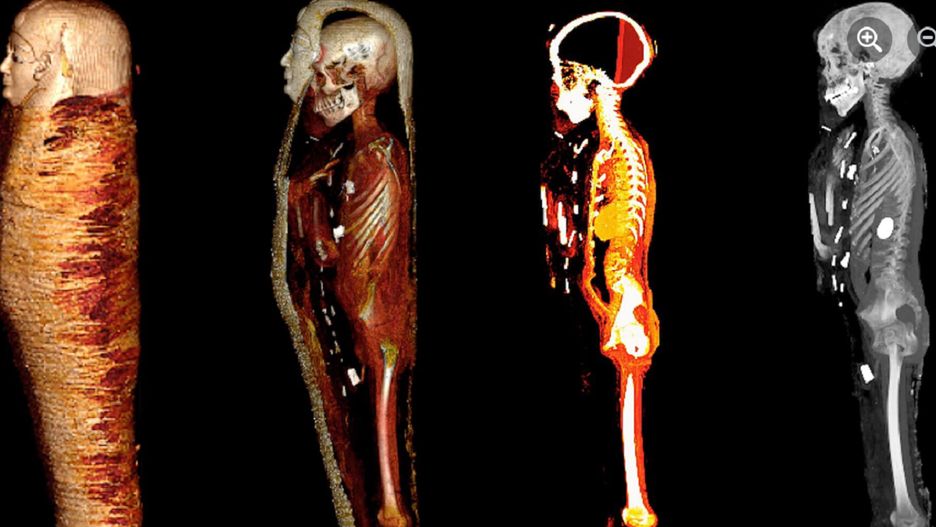

Ciało zmumifikowanego człowieka znaleziono na nekropolii w Nag el-Hassay przeszło sto lat temu. Teraz naukowcy przeanalizowali wnętrze mumii bez jej otwierania. Wykorzystali do tego tomografię komputerową. To kilkunastoletni chłopiec, na ciele którego dostrzegli 49 amuletów i złotą maskę!

Teraz naukowcy z Uniwersytetu w Kairze, pod wodzą Sahar Saleem, zdecydowali się przeprowadzić dokładne badania wnętrza mumii przy zastosowaniu tomografu komputerowego. Dzięki wykorzystaniu tej metody nie naruszyli zwojów oraz owiniętych nimi szczątków nieżyjącego człowieka. O sprawie pisze RMF FM.

Wyniki, które uzyskali dowodzą, że zmarły był w wieku zaledwie 14-15 lat. Świadczą o tym: stopień zrośnięcia jego kości w szkielecie oraz brak zębów mądrości. Przed pochówkiem usunięto mu wszystkie narządy wewnętrzne za wyjątkiem serca.

Skanowanie z użyciem tomografu ujawniło na jego twarzy złotą maskę, a na torsie złotą osłonę. Na nogach miał białe sandały. Badacze odkryli także, że ciało nastolatka pokrywa 49 różnorodnych amuletów. W usta wsadzono mu zaś złoty język, a na piersiach położono skarbeusza. Ich rolą w tamtych czasach była ochrona ciała oraz nadanie mu witalności w życiu.